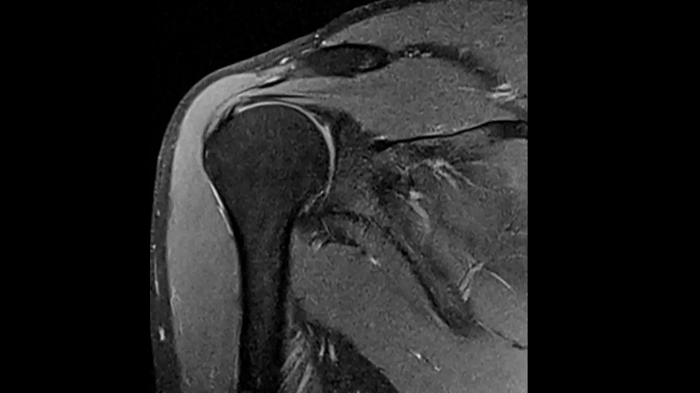

Shoulder

PD TSE Fat Sat with Deep Resolve and Simultaneous Multi-Slice

Exceptional fat suppression and performance for the shoulder’s clear imaging. Integrating the Deep Resolve’s power with the proven Simultaneous Multi-Slice technique.

SMS 2 | Deep Resolve Gain & Sharp

0.4 x 0.4 x 3.0 mm2

TA 3:20 minutes

MAC-ID: 7aaaa0213.

MAC-ID: 7aaaa0213. Image Credit: Siemens Healthineers